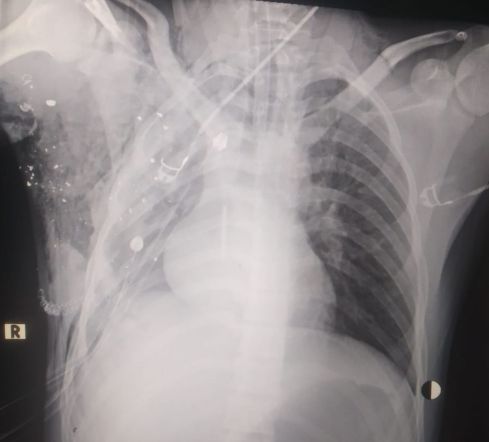

وافادت مصادر امنية لمراسل وفا، بأن قوات الاحتلال اقتحمت مدينة بيت جالا واندلعت مواجهات في محيط مستشفى بيت جالا الحكومي اطلقت قوات الاحتلال الرصاص وقنابل الغاز والصوت ما ادى لاصابة شاب (20 عاما) برصاص حي في الظهر، ونقل الى مستشفى الاهلي في مدينة الخليل لخطورة حالته.